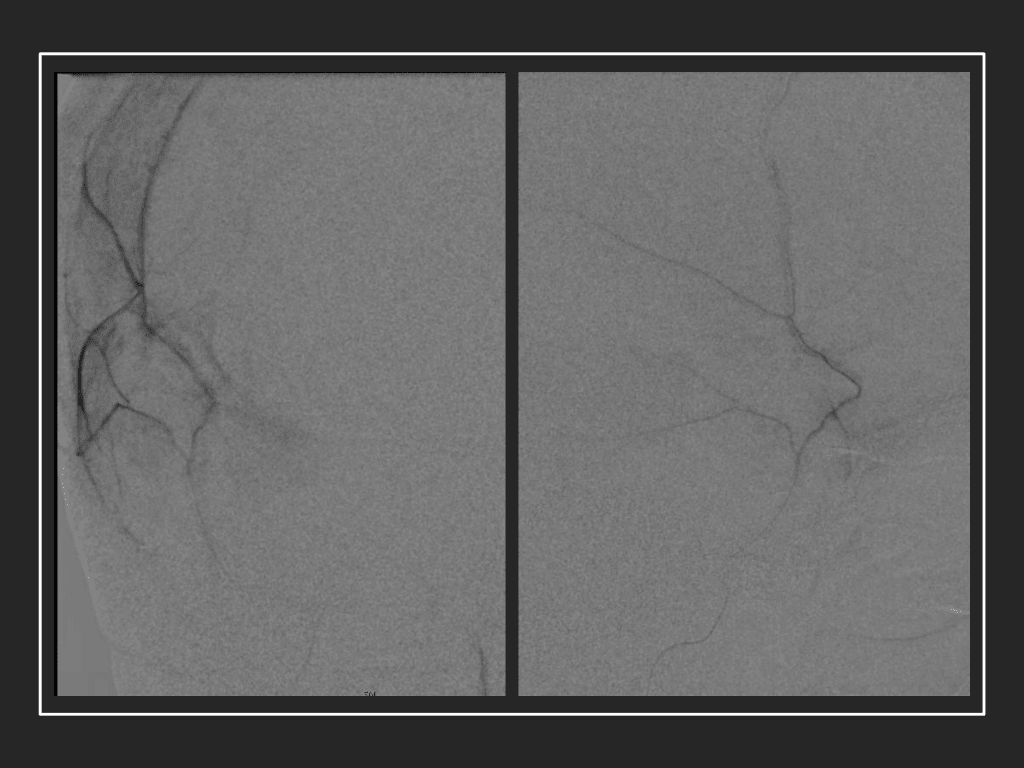

Figure 7. Neovascularized membranes within cSDH

Care must be taken to place the microcatheter within a safe position for embolization, with special attention to potential collateral branches to the orbit/eye via sphenoid or meningo-lacrimal branches (which may cause vision loss) or petrosal branches supplying the geniculate ganglion, the tympanic portion of the facial nerve, and often the trigeminal nerve via a branch coursing along the greater petrosal nerve. Once a safe position in the main trunk of the MMA, or superselectively in each of its divisions is achieved, embolization is performed until stasis of contrast and dense contrast staining of the dura is observed within the embolized vascular beds.7

Figure 8. Dense contrast staining of vascular membranes during embolization.